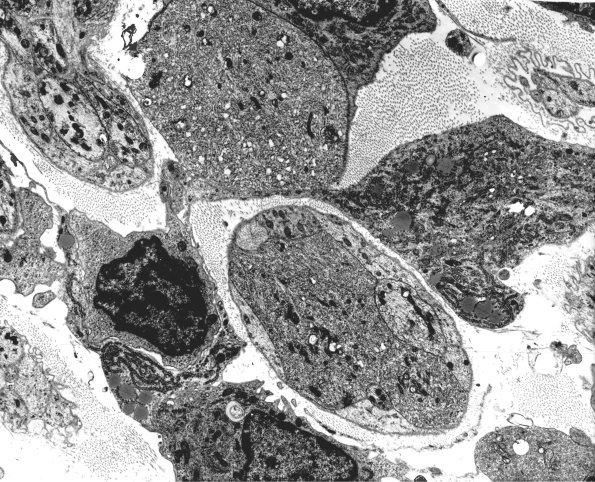

Washington University Experience | PERIPHERAL NEUROPATHY | 5 AXONAL REGENERATION | 2A3 Axons, regeneration (IV-55) Rat sciatic EM 64

2A3-6 Very large growth cones filled with densely compacted material were seen in obstructed regenerating axons. (electron micrographs)